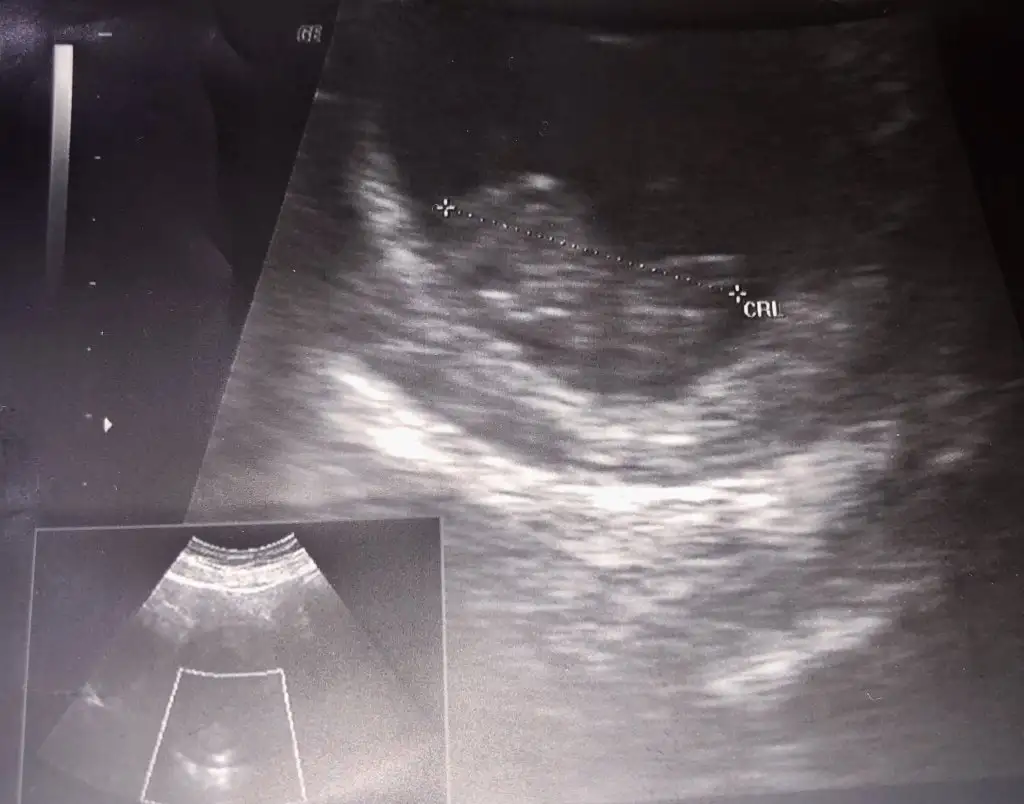

13 haftalık karından çekildiSelam Kızlarbir çok kişi gruplardan beni bilir. Yine yetiştim imdatlara

Çoook uzun bir süre araştırma okuma yaptıktan sonra sizlere bu başlığı açtım çevremde tüm gebelere de denedim. Bunun sırrını çözen İnstagramda (isim vermeyim) işi ticarete dökmüş bile.Nub, Ramzi,Çin Rus Japon Takvimleri, Yüzük Yöntemi bir çok şey size sayabilirim.

5 ve 14. haftaya kadar olan ultrason fotolarınızı paylaşın. Vajinadan mı yoksa karından mı çekildiğini ve kaç haftalık olduğunu da mutlaka belirtin.

Not: Tahmin yaptığım anneler cinsiyet öğrendikten sonra lütfen bana geri dönüş yapın